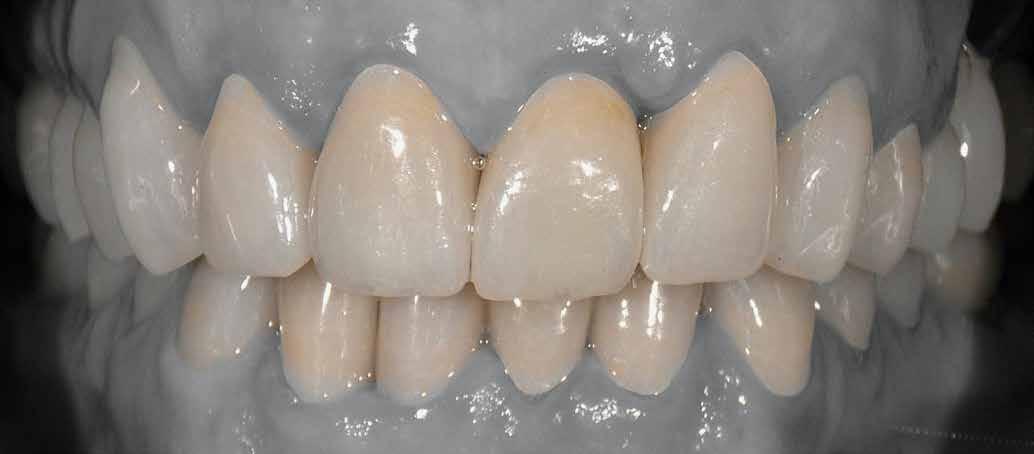

Az egyszárnyú ragasztott híd mellett döntöttünk (1. a kép)

Mivel a szemfogak általában nagyon közel vannak az antagonistához, kettes pótlására a szárnyat inkább a nagymetszőre szoktuk tervezni. Ehhez persze invazív preparációra van szükség – érintetlen fogak esetén ez lehetőleg kerülendő.

A bemutatott esetben azonban könnyen döntöttünk, mivel a szemfog disztális részén nagy tömés volt. A defektust bevontuk az eset megoldásába.

Végezetül részletfelvételek egy másik ragasztott hídról, amely hasonló módon készült, hat hónappal a behelyezés után (42–43. képek)

A hídtag enyhe mozgathatósága miatt az íny stimulálva volt. Ezzel a vérellátás további segítséget kapott, ami a lágyszövet kiváló adaptálódását hozta magával.